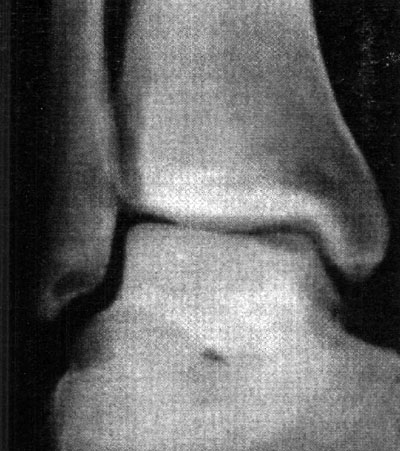

En cuanto a la localización de la lesión, 1 (2,4%) paciente presentó una localización anterior, 12 (29,3%) anterolateral, 23 (56,1%) posteromedial y 5 (12,2%) central. No se pudo explicar claramente esta distribución. (fotos 1 y 2) En cuanto a los casos presentados, los estudios radiográficos pusieron en evidencia la lesión en solo 36,6% de los pacientes, en 26 (63,4%) las radiografías fueron negativas (GI) mientras que de los casos positivos, 6 (14,6%) presentaron una lesión GIl, 6 (14,6 %) presentaron una lesión GIl y 3 pacientes (7,3%) una lesión G IV. (fotos 3 y 4)

Foto 3: RX Lesión G III

Foto 4: Lesión G IV Visualizada en T.A.C.